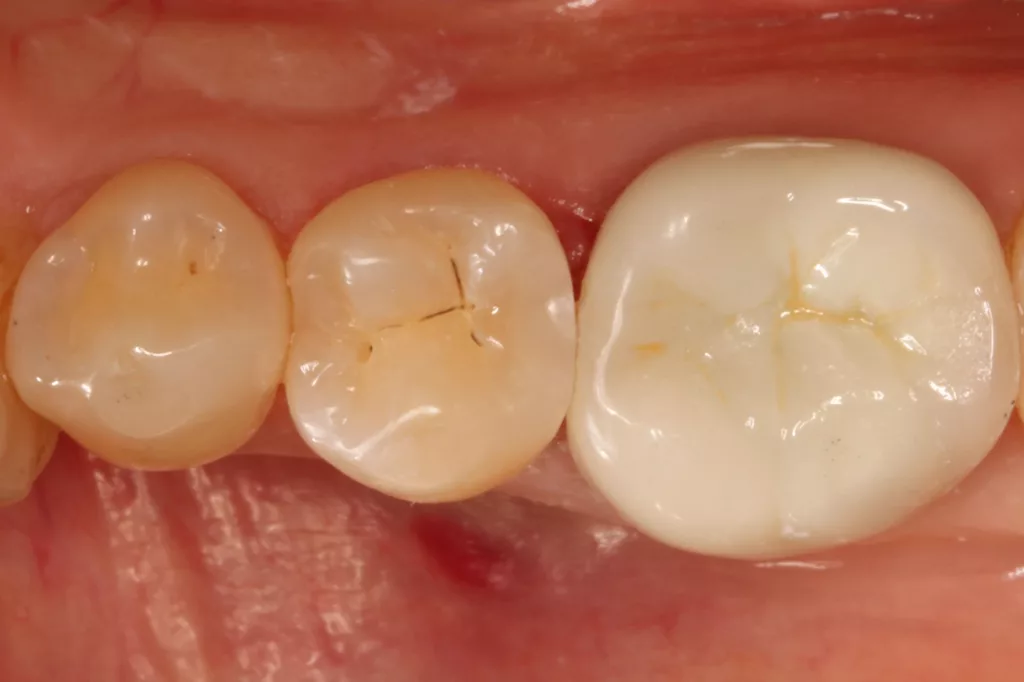

Die Verwendung des Kofferdams ist generell eine sehr empfehlenswerte, aber keine zwingende Voraussetzung zur Etablierung einer suffizienten Kontaminationskontrolle [47,96]. Das bisher auch bereits verwendete Zwei-Schritt-Universaladhäsiv G2 Universal wurde hier in der selektiven Schmelzätztechnik angewendet, d.h., das Material arbeitet auf dem Dentin selbstkonditionierend (Abb. 25). Die bislang zu diesem innovativen Mehrflaschen-Universaladhäsiv publizierten Daten zeigen eine beeindruckende Performance, die den Vergleich mit sogenannten Goldstandards [98] wie einem Optibond FL nicht scheuen müssen [13,18,34,58,63,114,119,127,130]. Im nächsten Schritt wurden die einzelnen Höcker mit dem angenehm standfesten Flowable aufgebaut (Abb. 26). Die Abbildung 27 zeigt die komplett versorgte okklusale Kavität, die Abbildung 28 die Situation unmittelbar nach Ausarbeitung und Politur. Erneut beeindruckt die gute Farbadaptation.